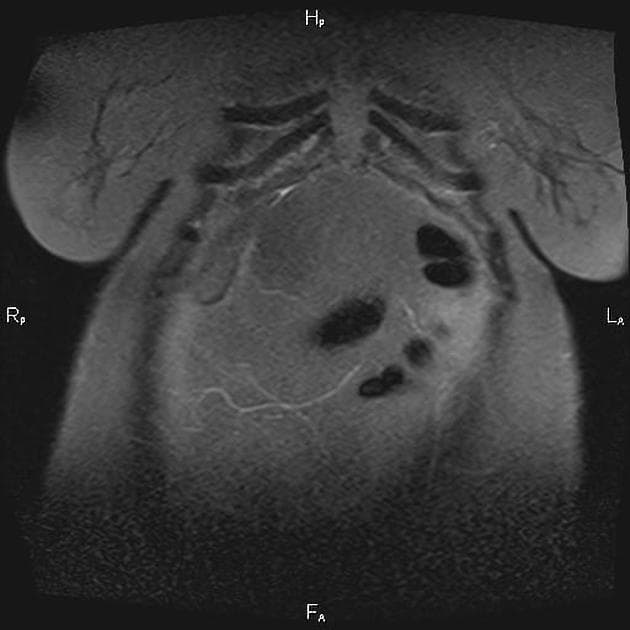

CT/MRI

Các hình ảnh tương tự như siêu âm, nhưng có khả năng tốt hơn trong việc phát hiện tổn thương trong gan và các biến chứng.